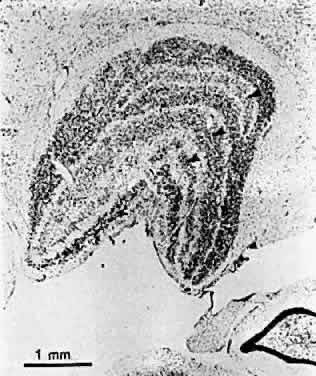

Hubel and Wiesel's first studies of monocularly lid-sutured kittens revealed unexpectedly that cell bodies in the lateral geniculate nucleus (LGN) that received input from the deprived eye were considerably smaller than those of cells in adjacent laminae the input of which came from the nondeprived eye (Fig. 16). This observation has been confirmed by many investigators in a number of species, including humans, and for every form of unilateral visual deprivation.72,80 It is generally believed to be a reflection of the decreased extent of the geniculocortical cells' terminal axonal branches in the visual cortex (corresponding to contracted cortical dominance columns). Reverse lid suturing of the normal eye after an initial period of monocular deprivation in the monkey has been shown to reverse the cortical ocular dominance shift without reversing the LGN changes.81 This suggests that there is some degree of independence between the two levels and greater or more prolonged plasticity in the cortex.

Fig. 16. Coronal section through the right lateral geniculate nucleus of the same monkey shown in Figure 15. Atrophy in the layers receiving input from the deprived eye is indicated by arrows. (Wiesel TN. Postnatal development of the visual cortex and the influence of environment. Nature 1982;299:583.)